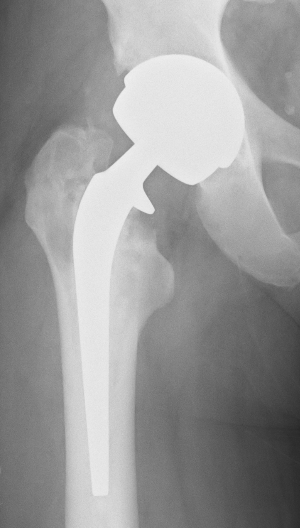

The Spectron Cemented Revision System - from http://www.hipsforyou.com/s&nrevisionsystems.php

In particular this page [click here] had the information I needed – and I immediately recognised the shape of the femoral stem prosthesis.

Take a look at the Spectron cemented revision system for total hip replacement by Smith & Nephew or you can download the three pages as a PDF here [click here].